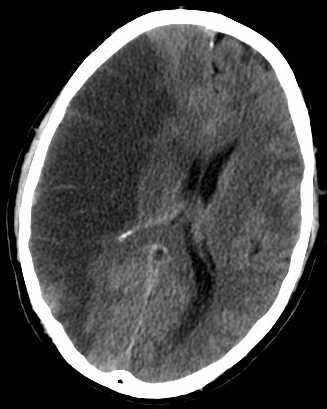

Un accident vasculaire cérébral résulte de l’arrêt de la circulation sanguine dans le cerveau, généralement quand un vaisseau sanguin est bloqué par un caillot dans 85% des cas ou éclate dans 15% des cas. Par conséquent, il y a un arrêt de l’apport en oxygène et en nutriments entrainant l’endommagement des tissus cérébraux.